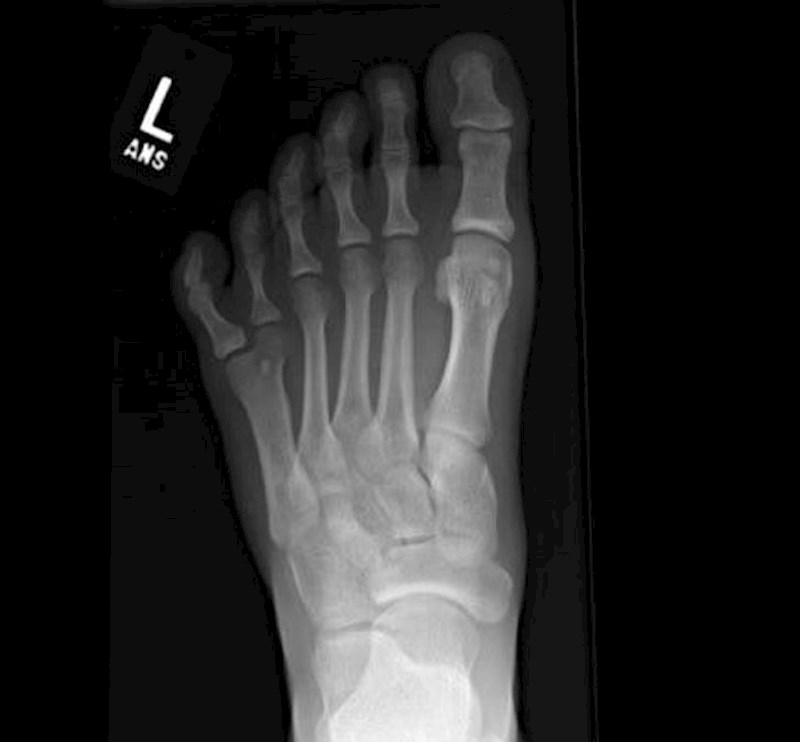

Snimka stopala sa 6 prstiju